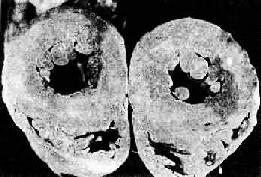

2.心脏的病变 主要为左心室肥大,这是对持续性血压升高,心肌工作负荷增加的一种适应性反应。在心脏处于代偿期时,肥大的心脏心腔不扩张,甚至略微缩小,称为向心性肥大(concentric hypertrophy)。心脏重量增加,一般达400g以上,甚至可增重1倍。肉眼观,左心室壁增厚,可达1.5~2cm;左心室乳头肌和肉柱明显增粗(图8-11)。镜检下,肥大的心肌细胞变粗,变长,并有较多分支。细胞核较长、较大(可形成多倍体)。由于不断增大的心肌细胞与毛细血管供养之间的不相适应,加上高血压性血管病,以及并发动脉粥样硬化所致的血供不足,便导致心肌收缩力降低,逐渐出现心腔扩张,称为离心性肥大(eccentric hypertrophy)。严重者可发生心力衰竭。

高血压病时左心室向心性肥大(心脏横断面)

图8-11 高血压病时左心室向心性肥大(心脏横断面)

左心室壁增厚,乳头肌显著增粗